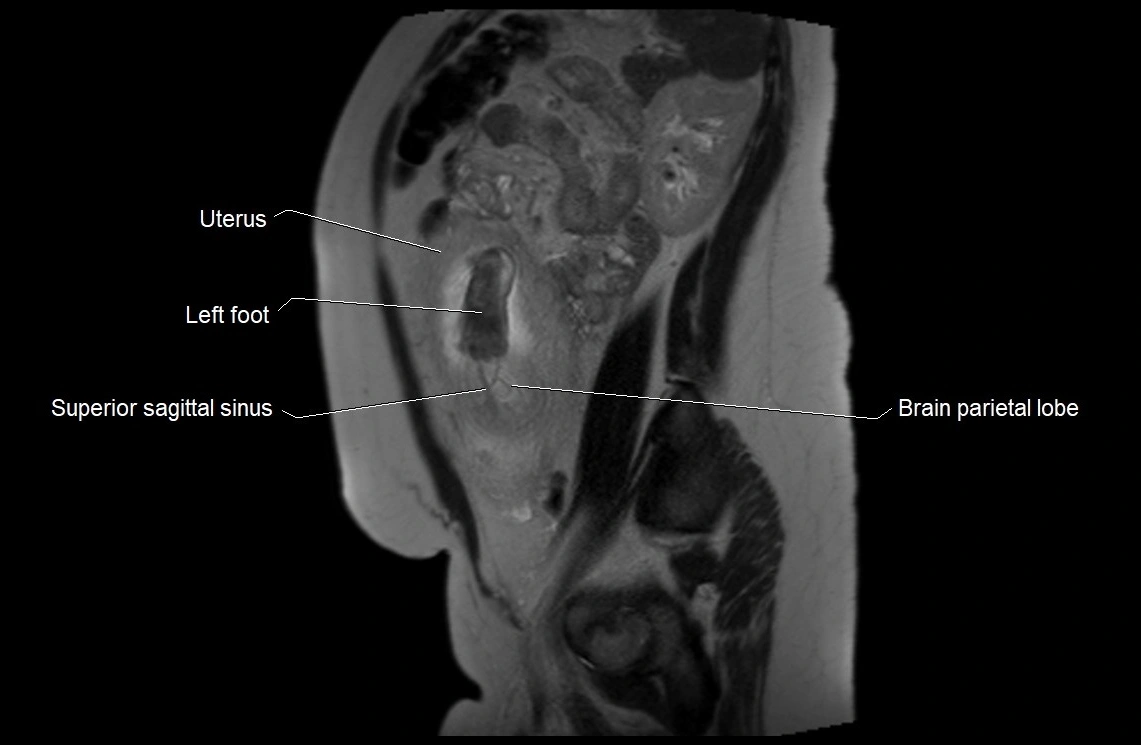

MRI Appearance

T2 HASTE (T2 GRE):

• Amniotic fluid shows very bright hyperintense signal

• Provides natural contrast against fetus and placenta

• Small particles (vernix) may appear as scattered hypointense foci within bright fluid

T1 GRE:

• Amniotic fluid shows low signal intensity (dark)

• Hemorrhage, infection, or proteinaceous content may cause focal or diffuse high signal intensity